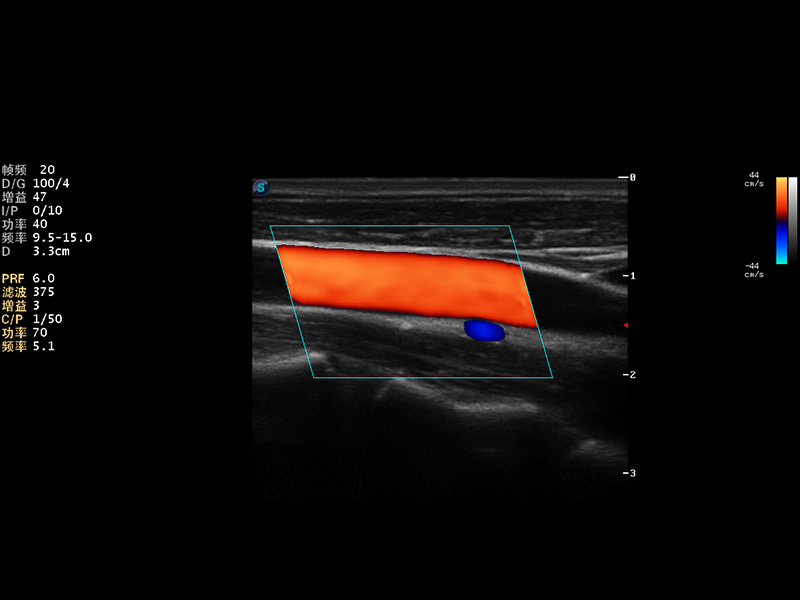

AutoC智能血流追踪

μ-Scan微米成像